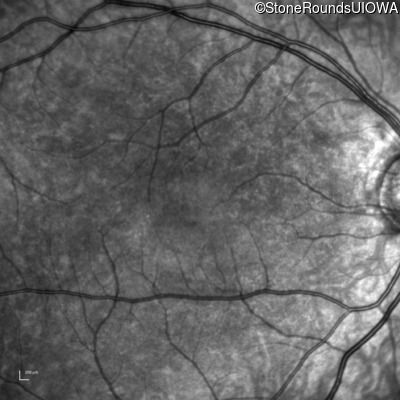

Infrared Fundus Photograph - Right - 10/160 sc

Exemplar